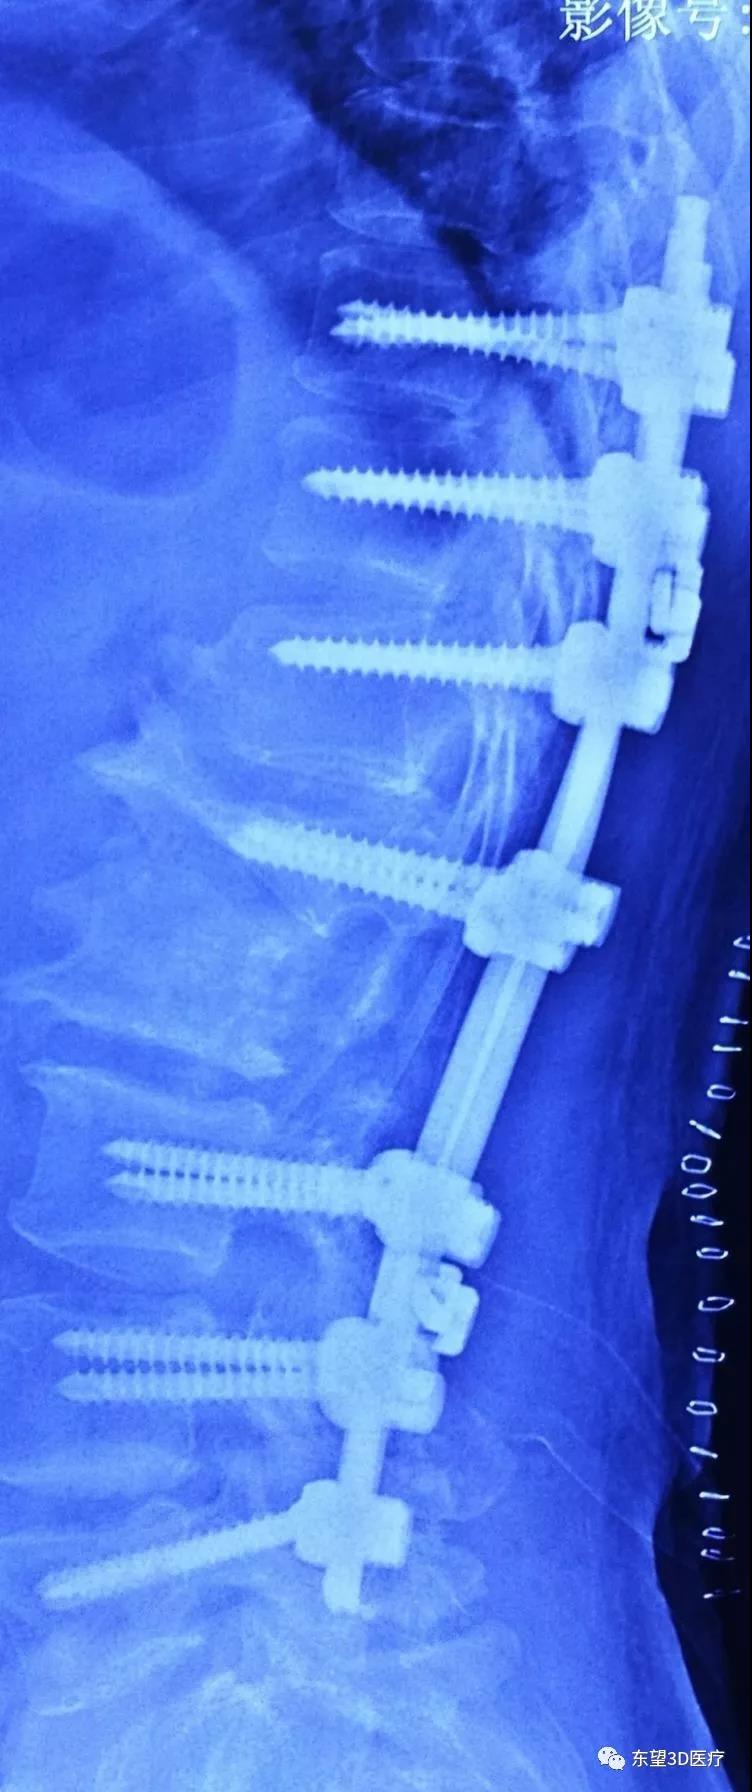

術中腰2椎體經椎弓根截骨(PSO),腰1-3椎體間融合,胸10-12腰3-5后柱融合

\

術后側位X片見后凸畸形消失,生理曲度恢復

術后正位X片見側凸及旋轉畸形消失,矯形理想。患者雙下肢疼痛麻木明顯好轉、肌力增加活動靈活,患者及家屬滿意。